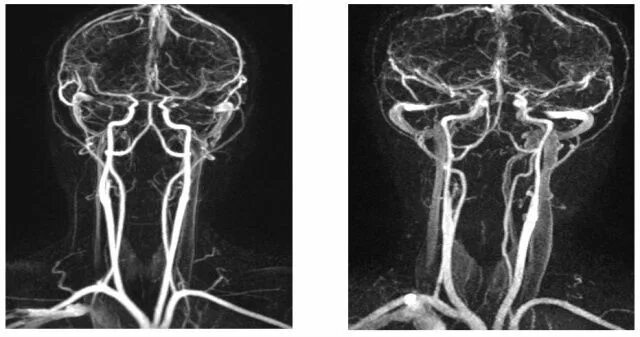

Асимметрия сегментов v2 позвоночных артерий